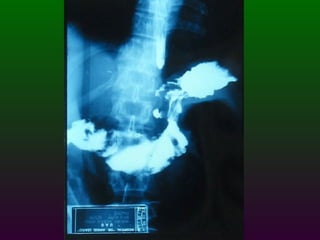

SEGD ENFERMEDADES DEL ESTÓMAGO Y DUODENO DIVISIÓN ANATÓMICA DEL ESTÒMAGO CARDIAS  FONDO CUERPO  ANTRO  PÍLORO

SEGD ENFERMEDADES DEL ESTÓMAGO INFLAMACIÓN NEOPLASIAS: Pólipos benignos Carcinoma Linfoma Leiomiomas TRASTORNOS DIVERSOS: Gastritis atrófica Crónica:   Gastritis hipertrófica   Gastritis cáustica   Vólvulos

SEGD ENFERMEDADES DELESTÓMAGO Y DUODENO DIVISIÓN ANATÓMICA DEL ESTÒMAGO CARDIAS FONDO CUERPO ANTRO PÍLORO

SEGD ENFERMEDADES DELESTÓMAGO INFLAMACIÓN NEOPLASIAS: Pólipos benignos Carcinoma Linfoma Leiomiomas TRASTORNOS DIVERSOS: Gastritis atrófica Crónica: Gastritis hipertrófica Gastritis cáustica Vólvulos